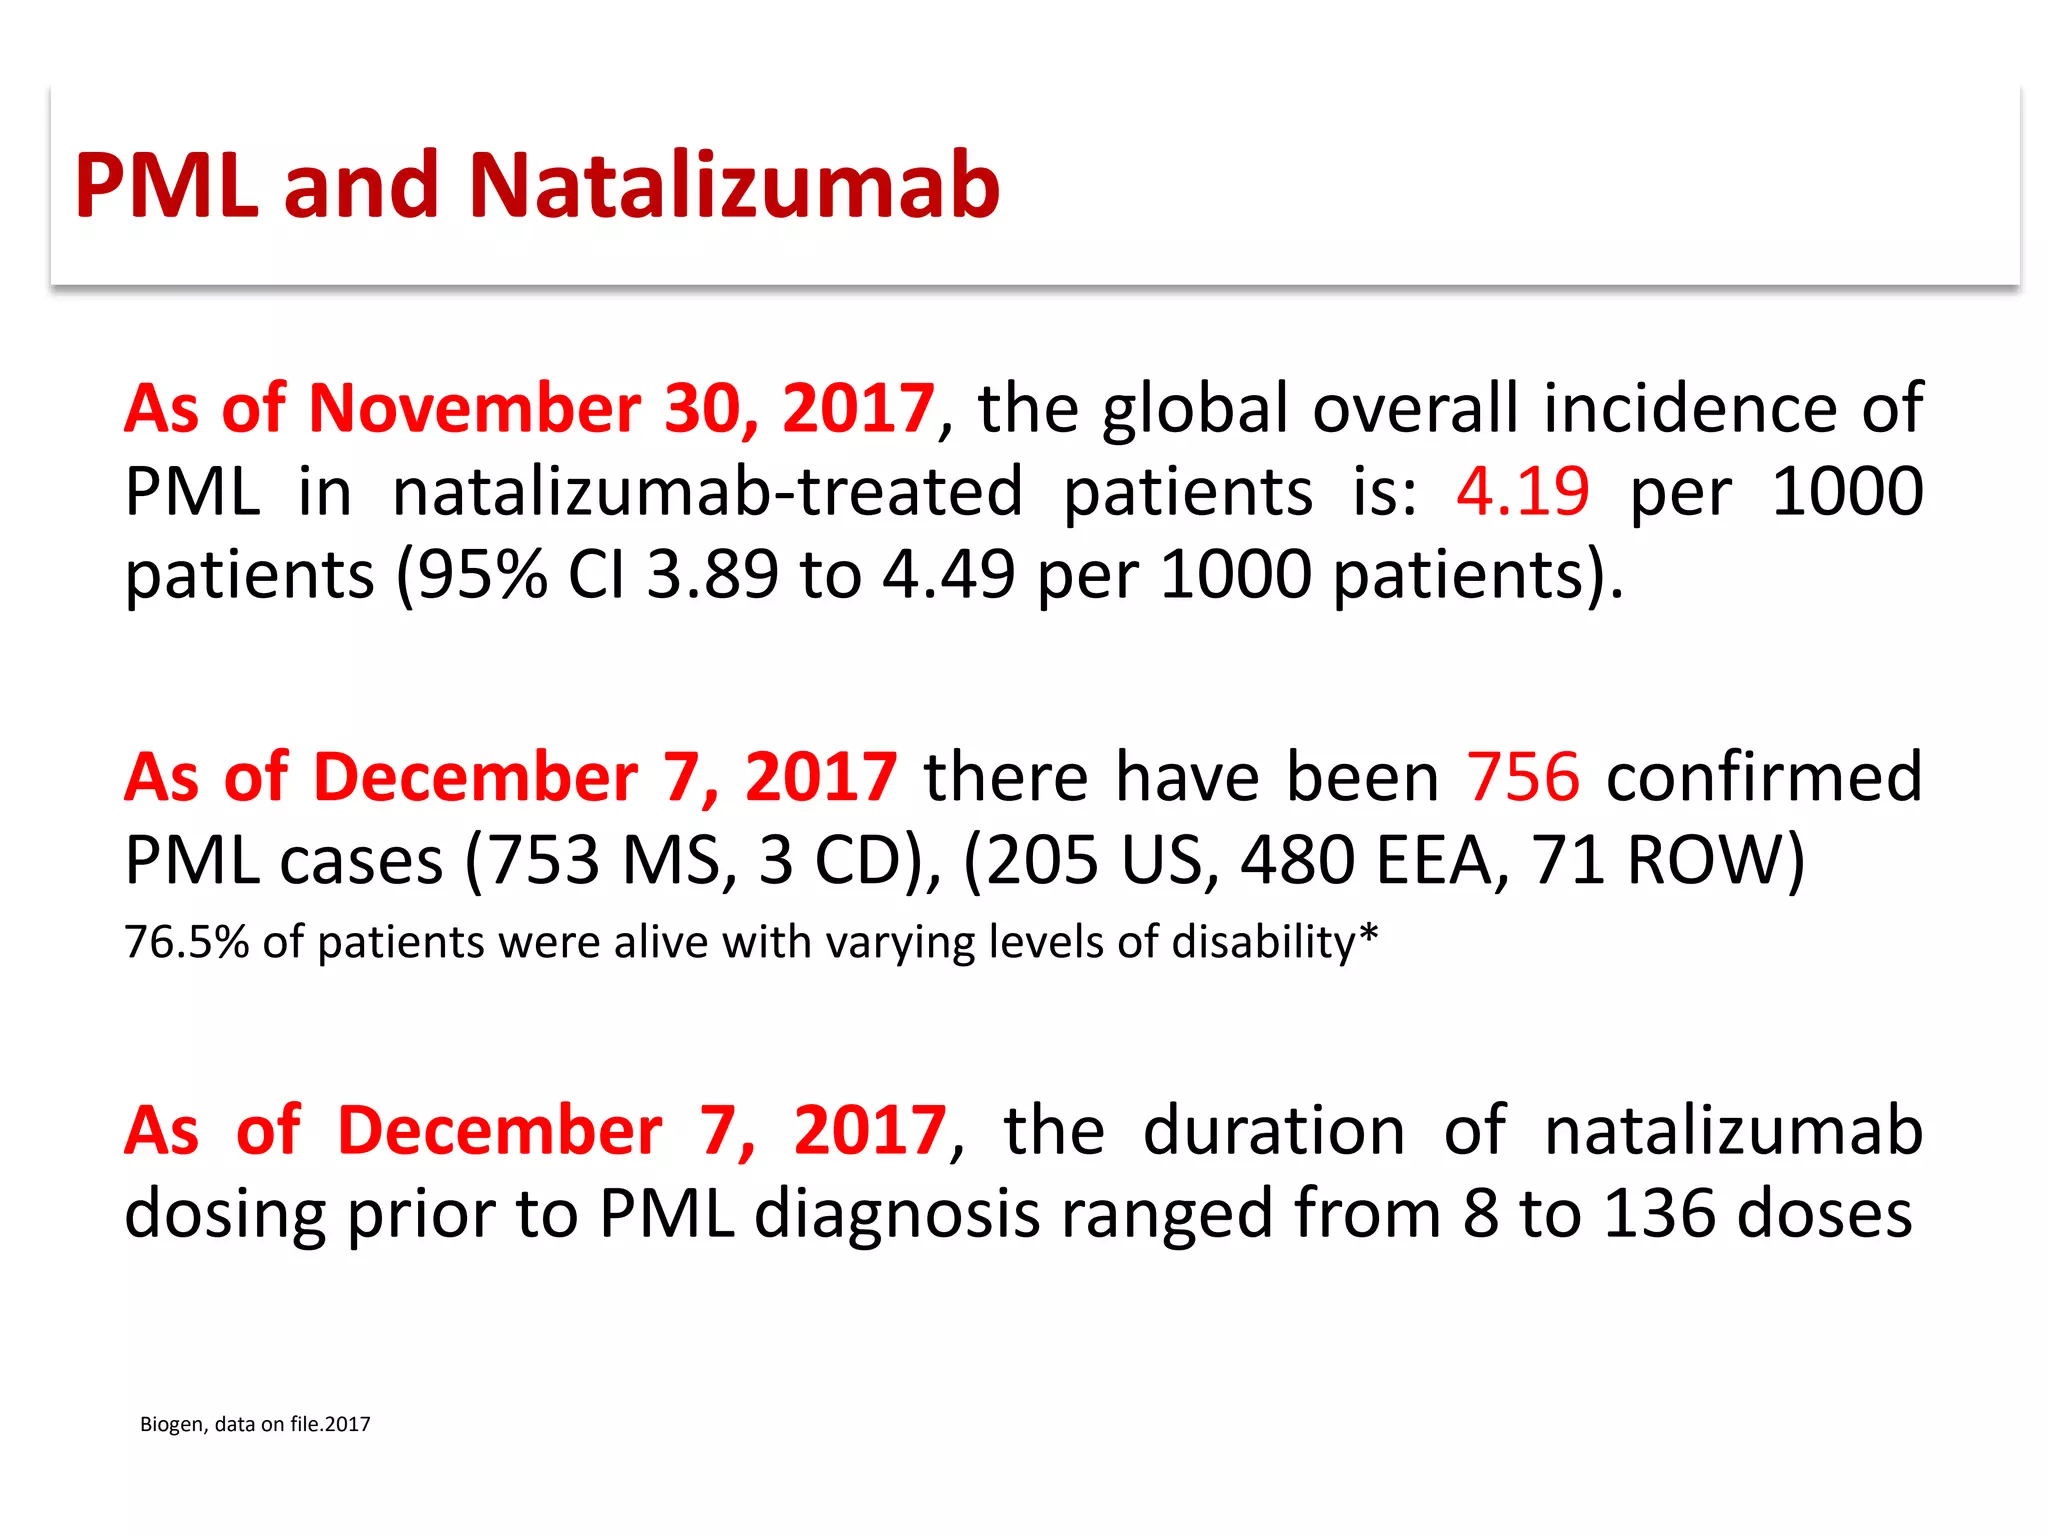

This document discusses progressive multifocal leukoencephalopathy (PML), an opportunistic infection caused by the John Cunningham virus (JCV) that leads to demyelination in the central nervous system. It highlights the epidemiology, clinical manifestations, diagnostic methods, and risk factors associated with PML, particularly in immunocompromised patients and those undergoing immunomodulatory therapies. It also presents data on the incidence of PML in patients treated with natalizumab and other therapies, addressing the relationships between these treatments and the development of PML.